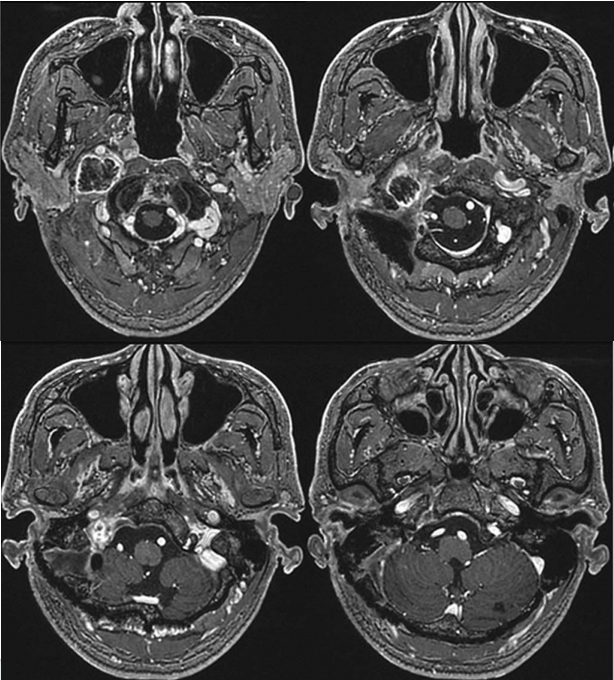

另一例为15岁青少年患者小凯,临床表现为声音嘶哑、扁桃体炎、耳痛及持续性头痛。药物治疗初期部分缓解症状但易反复。一月后复查发现颈静脉孔区神经鞘瘤生长。在巴教授主刀下行肿瘤全切术,术后恢复良好:术后2个月精神状态显著改善;术后6个月影像学评估显示肿瘤完全切除,脑干、血管及颅底结构保护完好,嗓音功能明显恢复;术后1年经耳鼻喉科专家评估及发声训练,声带问题显著改善。